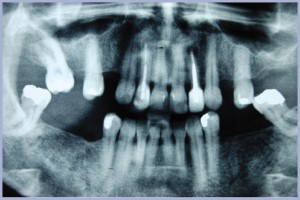

Nel giugno del 2011 si è presentata alla nostra osservazione, presso il reparto di implantologia dell’Università degli Studi di Cagliari, una paziente di 48 anni alla quale mancavano numerosi elementi dentari (Fig. 1). La richiesta della paziente è stata quella di poter essere riabilitata con protesi fissa, ma di dare precedenza all’incisivo laterale superiore destro che le procurava dolore e disagio estetico (Fig. 2).

- Fig. 1 – OPT iniziale